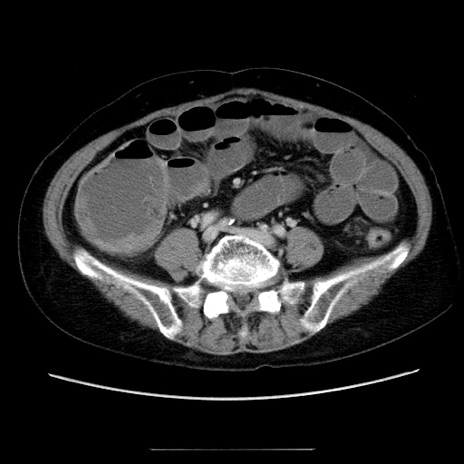

冠状断像

【症例】70歳代女性

【主訴】お腹が張る

【現病歴】1週間くらい前から腹部膨満の自覚あり。昨日夜から増悪したため、本日救急外来受診。

【身体所見】意識清明、BT 36.5℃、BP 165/106mmHg、HR 80bpm、SpO2 98%、腹部:膨満、軟、自発痛・圧痛なし、触診にて不快感あり、腸蠕動音:減弱

【データ】WBC 12600、CRP 1.04